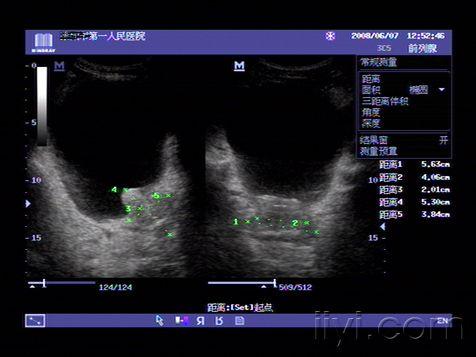

超声入门贴70-----前列腺测量方法

典型前列腺增生症超声图片

16楼回复飘逸前列腺超声检查测量方法与正常值 正常前列腺的超声测值

前列腺超声检查